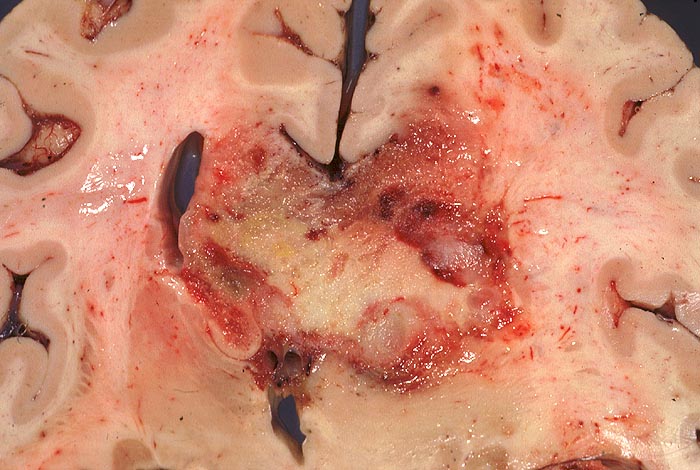

Die Schnittfläche ist auffallend bunt. Dies ist bedingt durch ein Nebeneinander von graurotem vitalem Tumorgewebe, gelben Nekrosen, roten Einblutungen und gelegentlich grünlichen Gallertzysten.

Das MRI mit Kontrastmittel ist die radiologische Untersuchungsmethode der Wahl. Im CT zeigt sich eine zentrale dunkle Nekrosezone umgeben von einer ringförmigen Kontrastmittelanreicherung entsprechend der stark vaskularisierten vitalen Peripherie des Tumors. Der Ring zeigt aber nicht die Grenze des Tumors an. Tumorzellen findet man auch noch bis zu 2cm ausserhalb dieser Zone.

• Zellreicher Tumor mit sehr unscharfer Begrenzung zum normalen Hirnparenchym (rechts unten).

• Typische streifenförmige Nekrosen mit randständiger Palisadierung der Tumorzellen.

• Im Zentrum der Nekrose thrombosierte Gefässe umgeben von einem Saum vitaler Tumorzellen.